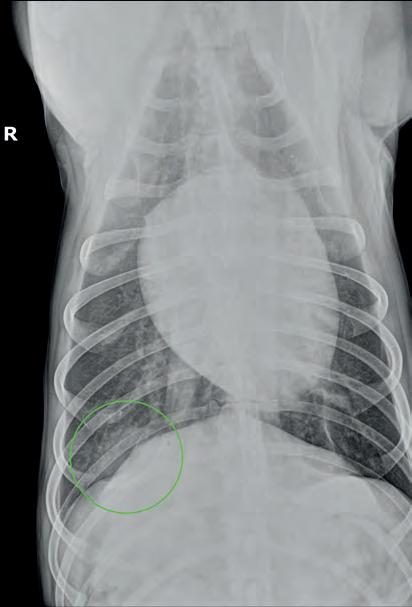

Se presenta un labrador hembra esterilizada de 6 años a mediados del mes de agosto en la región de Madrid, con historial de fiebres recurrentes de 15 días de evolución a la cual se le realizaron pruebas de enfermedades infecciosas transmitidas por vectores (Ehrlichia, Anaplasma, Filaria y Leishmania) con resultados negativos. Se administró antibioterapia de amplio espectro y antiinflamatorios no esteroideos y las fiebres cesaron puntualmente. Su centro veterinario la remitió porque al terminar el tratamiento la paciente volvió a mostrar decaimiento y fiebre de 39,7 ºC. Analíticamente presentaba leucocitosis neutrofílica severa (30,96 x 109/l; RR: 6,00-17,00 x 109/l) y un panel bioquímico sin alteraciones reseñables. Se realizó proteína C reactiva con valor superior a 150 mg/dl (RR: 1-10 mg/dl). Se realizó estudio ecográfico abdominal que no presentaba alteraciones. Se realizó un estudio radiográfico de tórax con proyecciones lateral derecha y ventrodorsal (Fig. 1).

Figura 1. Radiografías de tórax de la paciente en proyección lateral derecha (A) y ventrodorsal (B). Fallo en la técnica: Presencia de la letra indicativa del decúbito en superposición con la paciente.

En la proyección lateral derecha se evidencia un patrón intersticial no estructurado en el aspecto dorsal de los lóbulos pulmonares caudodorsales que impide la correcta visualización del pilar diafragmático derecho a dicho nivel; en este caso, la proyección presenta una rotación significativa la cual posiblemente haya permitido visualizar la lesión radiológica con mayor claridad (Fig. 2A). Asimismo, en la proyección ventrodorsal se localiza en la zona de proyección del lóbulo pulmonar caudal derecho un foco de patrón intersticial no estructurado junto a una lesión de tipo nodular y bordes mal definidos, en la zona de proyección de la décima costilla (Fig. 2B). Se observa, además, la presencia de fisuras pleurales, indicativas de efusión pleural leve bilateral. El resto de las estructuras evaluables no muestran alteraciones reseñables.

Diagnósticos compatibles con los signos radiográficos observados (diagnóstico diferencial) Los hallazgos observados incluyen un patrón intersticial no estructurado con interrupción del pilar diafragmático derecho, junto con un patrón estructurado de tipo nodular de 25 x 54 mm, ambos localizados en la porción caudodorsal del lóbulo pulmonar caudal derecho. Estos hallazgos sugieren los siguientes diagnósticos diferenciales: absceso/granuloma pulmonar, tromboembolismos pulmonares, tumores pulmonares

primarios (carcinoma broncoalveolar, adenocarcinoma pulmonar, sarcoma histiocítico, carcinoma de células escamosas.), metástasis únicas de tumores primarios o un área única de consolidación pulmonar simulando un nódulo debido a una neumonía o bronconeumonía. Además, las fisuras pleurales indican la presencia de efusión en el espacio pleural, la cual puede ser de tipo trasudado puro (p. ej., hipoproteinemia), trasudado modificado (p. ej., neoplasias pulmonares/pleurales, quilotórax, trauma torácico), exudado (p. ej., piotórax) o de tipo hemorrágico.

(A) Radiografía de tórax en proyección latero-lateral

resaltado se observa un patrón intersticial no estructurado a nivel caudodorsal (círculo) que impide la correcta visualización del pilar diafragmático derecho. Además, se evidencia la presencia de fisuras pleurales (flechas). (B): Radiografía de tórax en proyección ventrodorsal; resaltado se evidencia un patrón estructurado de tipo nodular en la zona de proyección de la décima costilla (círculo).

Figura 2. Mismas radiografías

Figura 1.

derecha;